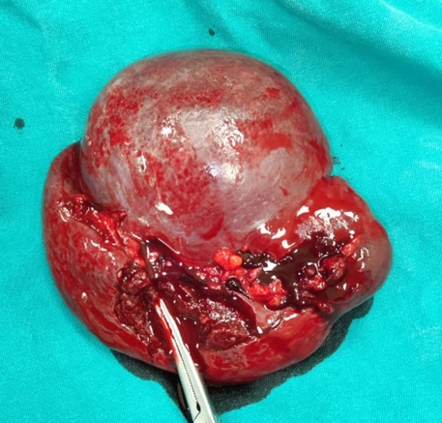

After a detailed preoperative evaluation, a splenectomy was recommended due to a vascular tumor of the spleen. There was no blood loss or injury to the tail of the pancreas during the procedure. The tumorous spleen specimen was completely removed (Figure 2).

Figure 2: Intraoperative image of the spleen specimen with tumor.